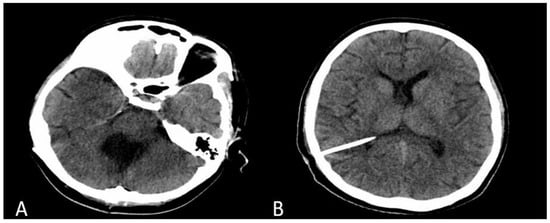

2. Case Presentation